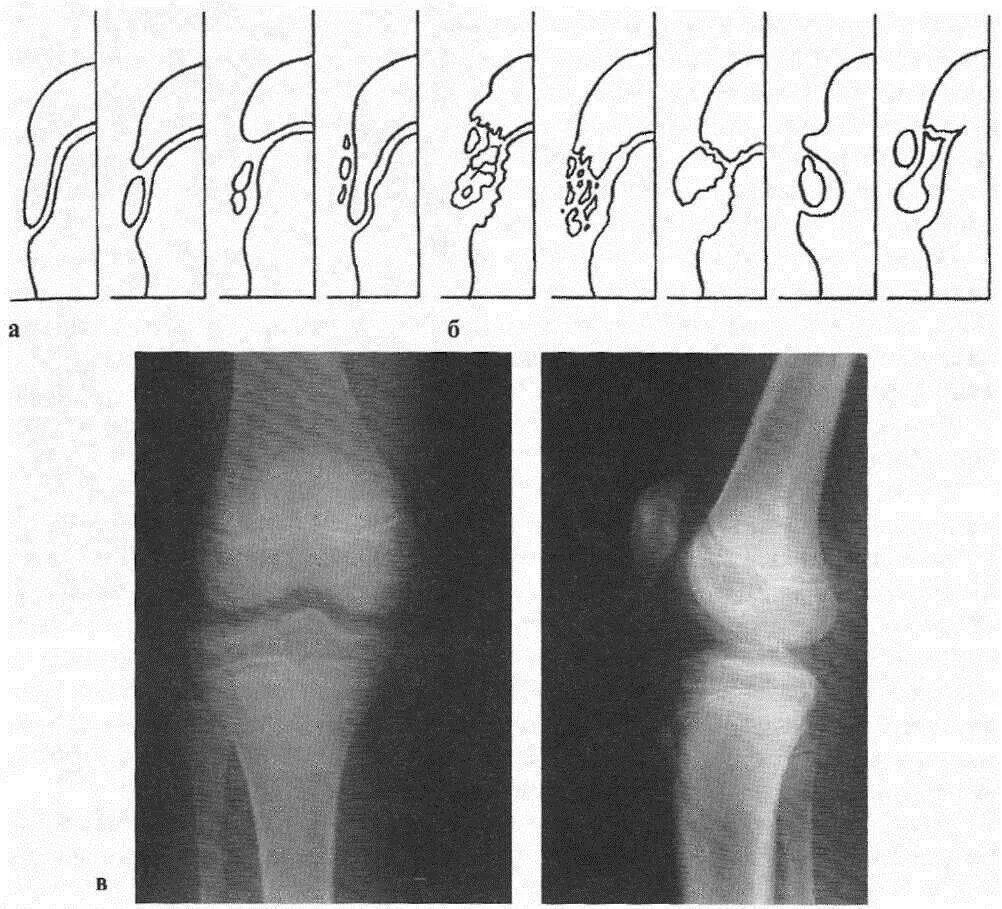

Код мкб шляттера